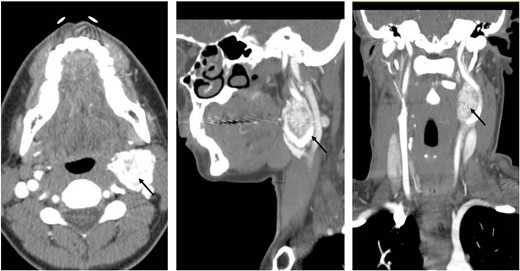

A 35-year-old woman presented with a 6-month history of a progressively enlarging, painless left neck mass. She reported no additional symptoms, including no fevers, night sweats, unexplained weight loss, hoarseness, or dysphagia. She had no significant past medical or family history and did not take any medications. Physical exam revealed a 3-cm well-circumscribed, hard, immovable, and nontender mass on the left lateral neck and no additional abnormalities. A CT scan of the neck and chest was ordered, which revealed a lobulated left cervical mass measuring up to 3.6 cm (Fig. 1). The patient was referred to vascular surgery for further evaluation.

Coronal, sagittal, and axial images showing the 3.6 × 3.5 cm mass splaying the left internal and left external carotid arteries.